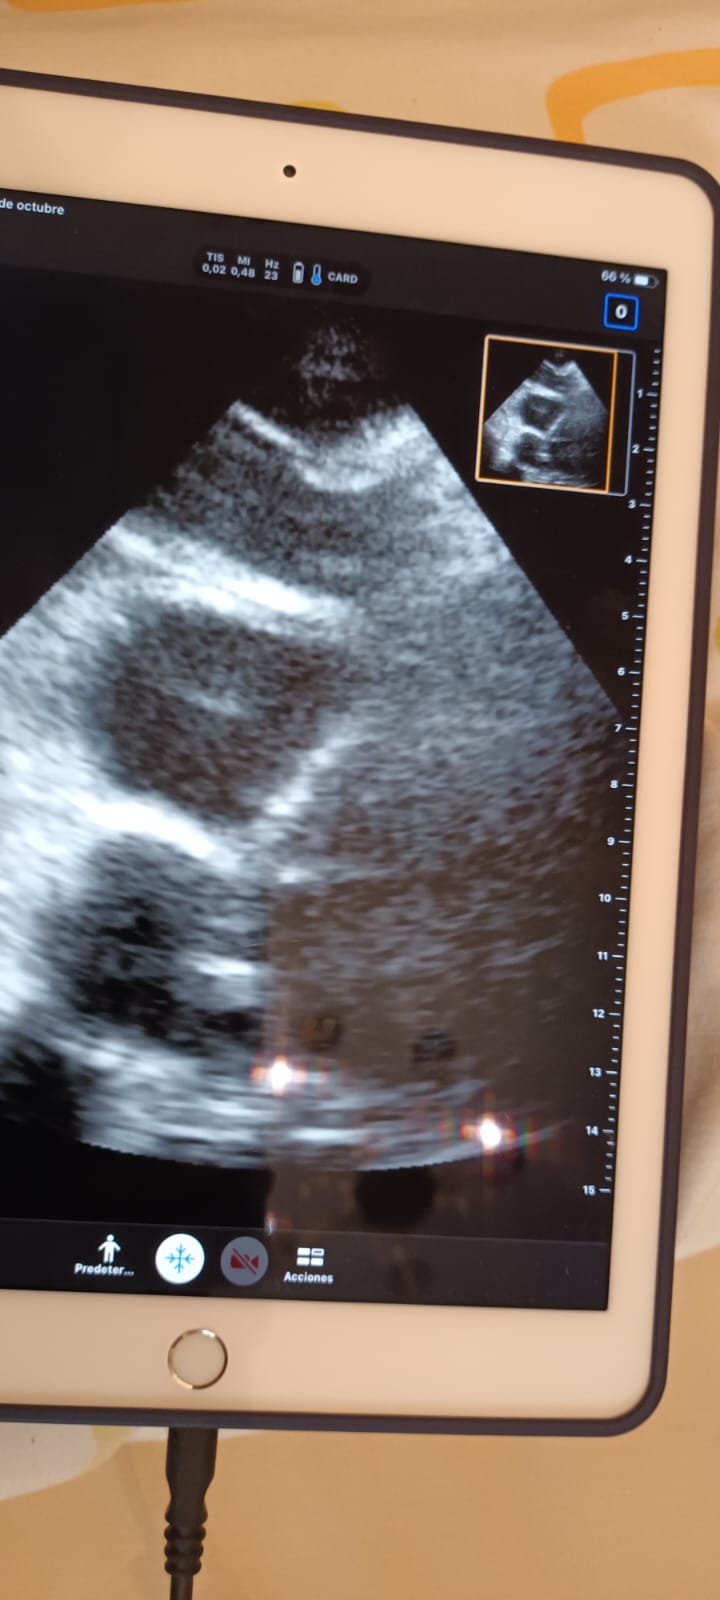

Realizamos también ecocardioscopia, encontrando un trombo en transición en ventrículo derecho.